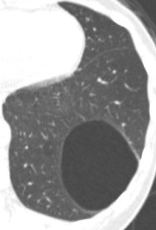

女性,50岁,2018年,体检巨大肺囊肿。2021年复查,囊肿缩小,后壁有10mm实性结节。2020年有高原旅行,剧烈疼痛病史。

2018年CT